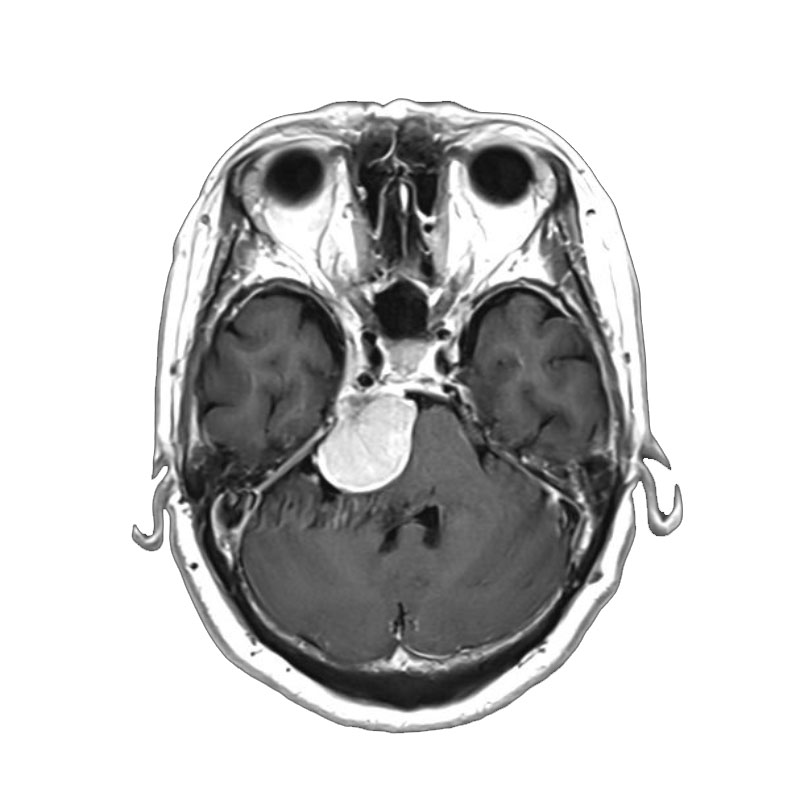

脳動脈瘤(Acom)

脳血管内手術

芝野/古谷/木本